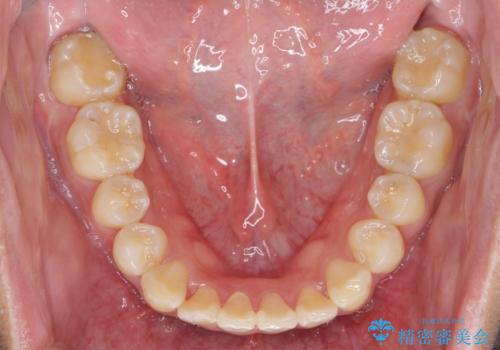

遠心移動を伴うマウスピース非抜歯矯正治療

- 「前歯の見た目を改善したい。」と矯正治療を希望され来院されました。

前歯のガタつきに加え、上顎が前にある咬合関係(上顎前突)を改善すべく、マイクロインプラントを用いた上顎奥歯の後方移動、拡大、ディスキングを用いたマウスピース矯正治療を計画します。

マイクロインプラントを使用したことで、しっかりと遠心移動が為され、良好な咬合関係が達成されました。